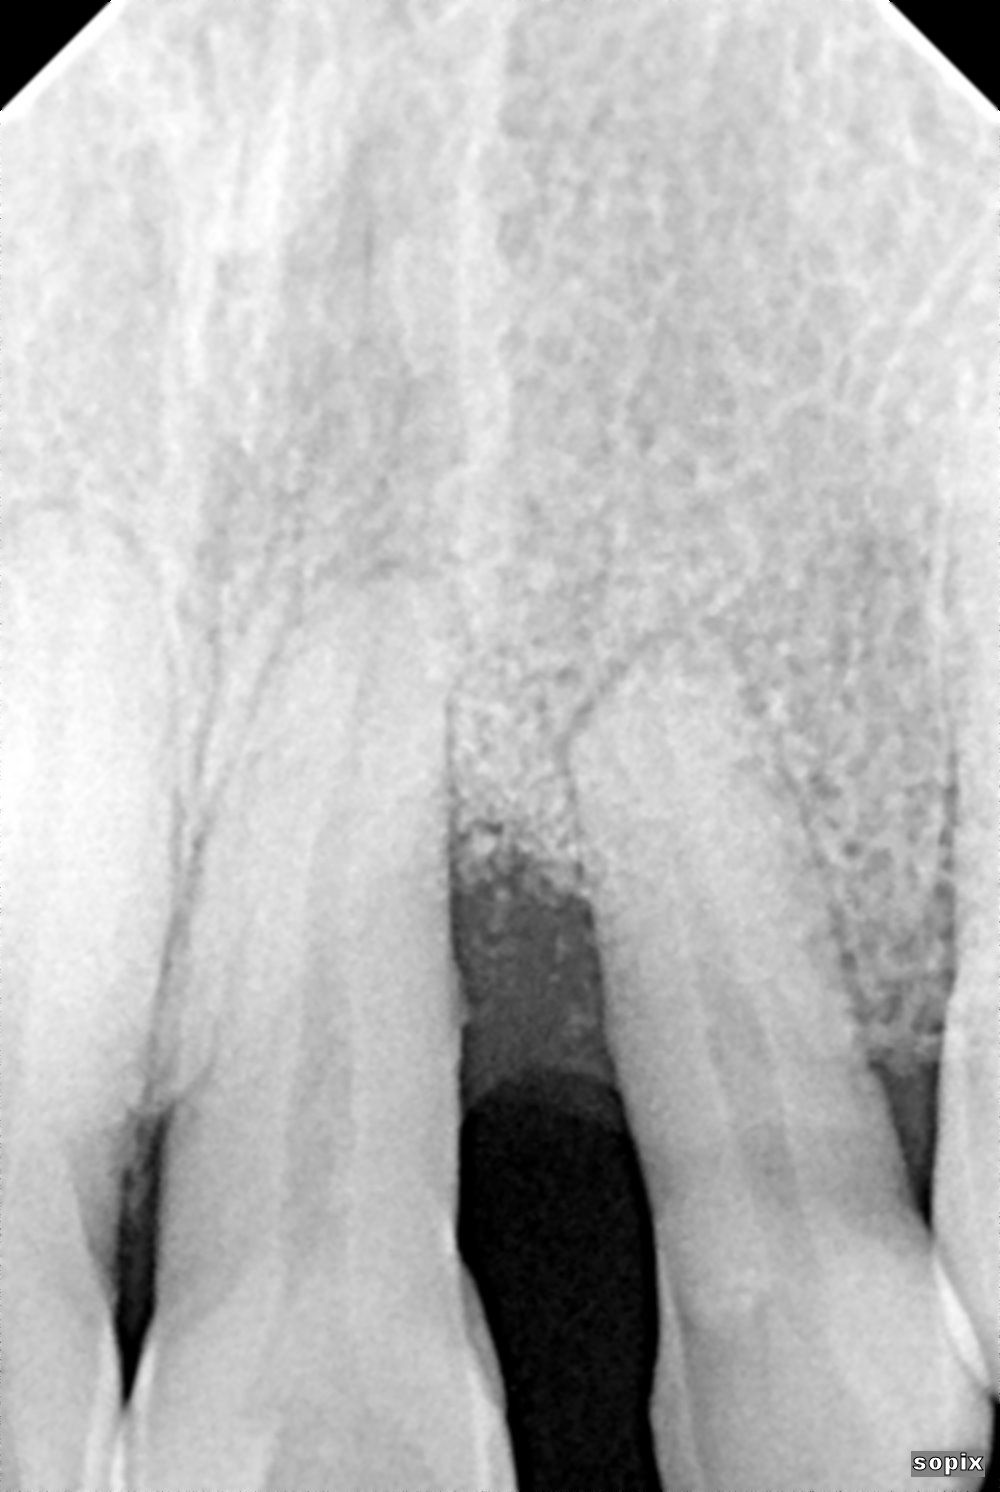

A 46-year-old male healthy (ASA I), non-smoker, with no medication, was referred to our practice for a papilla reconstruction in the anterior esthetic zone. The intraoral examination revealed a protruded and extruded tooth #22, localized erythema and edema at teeth #21 and #22, with a severe loss of the interproximal papilla. The periodontal examination revealed a PPD of 8 mm at teeth #21 and #22, and established a diagnosis of localized stage III, grade C periodontitis (Fig. 1). The radiographic examination revealed a severe vertical osseous defect (Fig. 2).

The patient paused his treatment due to the COVID-19 pandemic. The radiographic control two years after surgery revealed significant bone fill of the defect (Fig. 13), and the patient began orthodontic treatment.